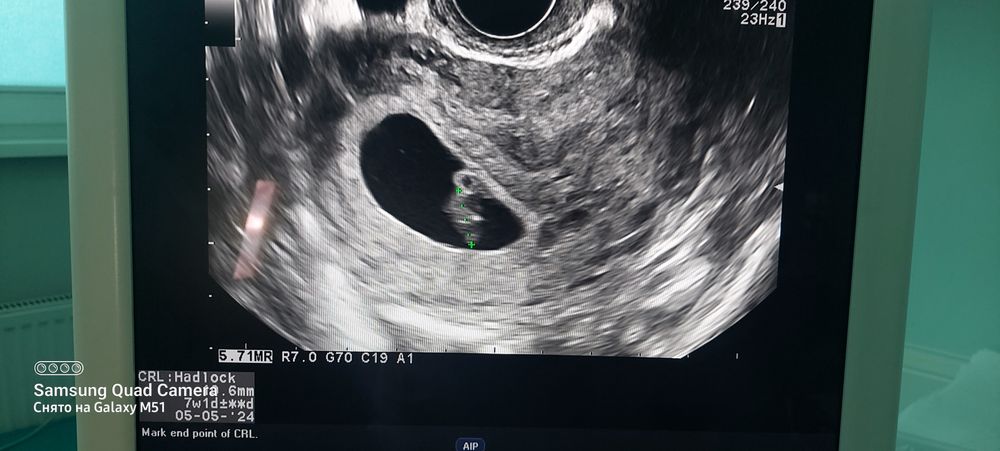

Юлия Перминова 2 года Мой малышунчик 10.6 мм 9 акушерских недель. Дату пдр поставили на 5 мая. Посмотрите еще 20 записей на эту тему Лучший ответ Юлия Перминова Судя по дате пдр то Малышок соответствует сроку 7.1 нед. 18.09.2023 Ответить Отменить Ответить Результаты анализов не радуют Тест на переносимость глюкозы Чаты Беременных Выберите чат: Январята-2026 Февралята-2026 Мартята-2026 Апрелята-2026 Майчата-2026 Июнята-2026 Июлята-2026 Августята-2026